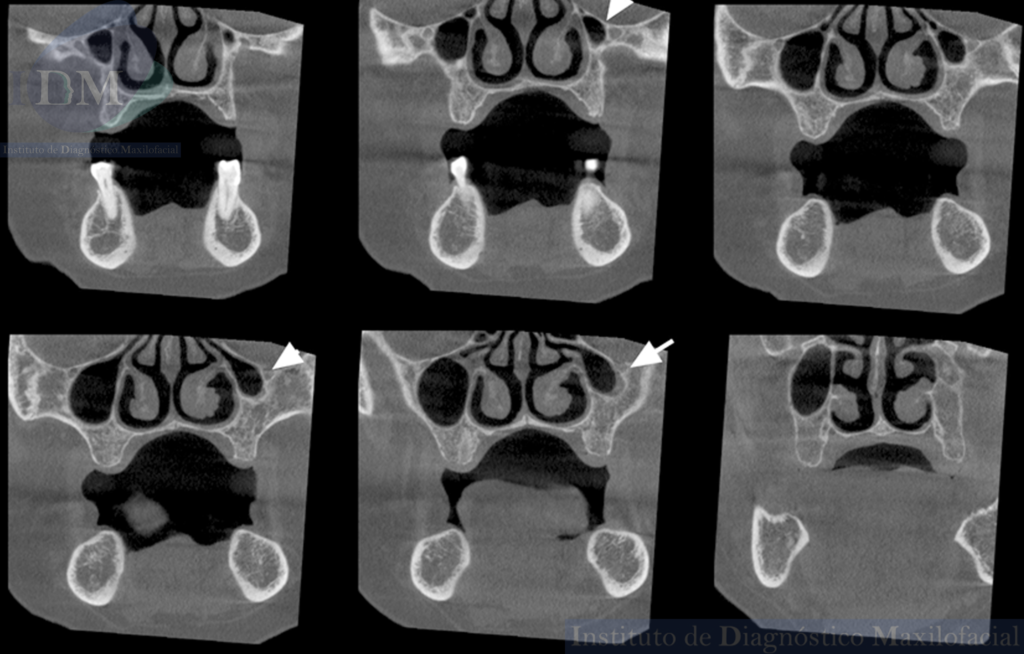

A la evaluación de la tomografía computarizada de haz cónico de campo mediano se observa la disminución de la longitud cefalo caudal y antero posterior del seno maxilar del lado izquierdo en comparación a su contralateral (visto en los cortes coronales y axiales respectivamente).

Asimismo, se observa el engrosamiento de la mucosa antral a predominio de la pared posterior que a su vez presenta una imagen hiperdensa de forma irregular compatible con probable Antrolito. Finalmente, en zonas edéntulas de premolares y molares del segundo cuadrante se observa el trabeculado óseo característico del maxilar superior que debería estar ocupado por el seno maxilar.

CORTES CORONALES